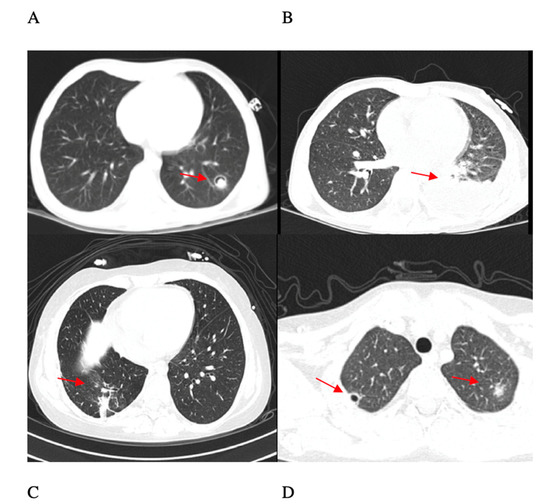

3.1. Index Case

| 5 | AML (M6) | 8 years/ M | First line AML therapy | Blood, lung, skin | Blood culture, histological analysis on lung lobectomy GM− | 7 | proven | No | Caspofungin + voriconazole (2 months) | Recovered |